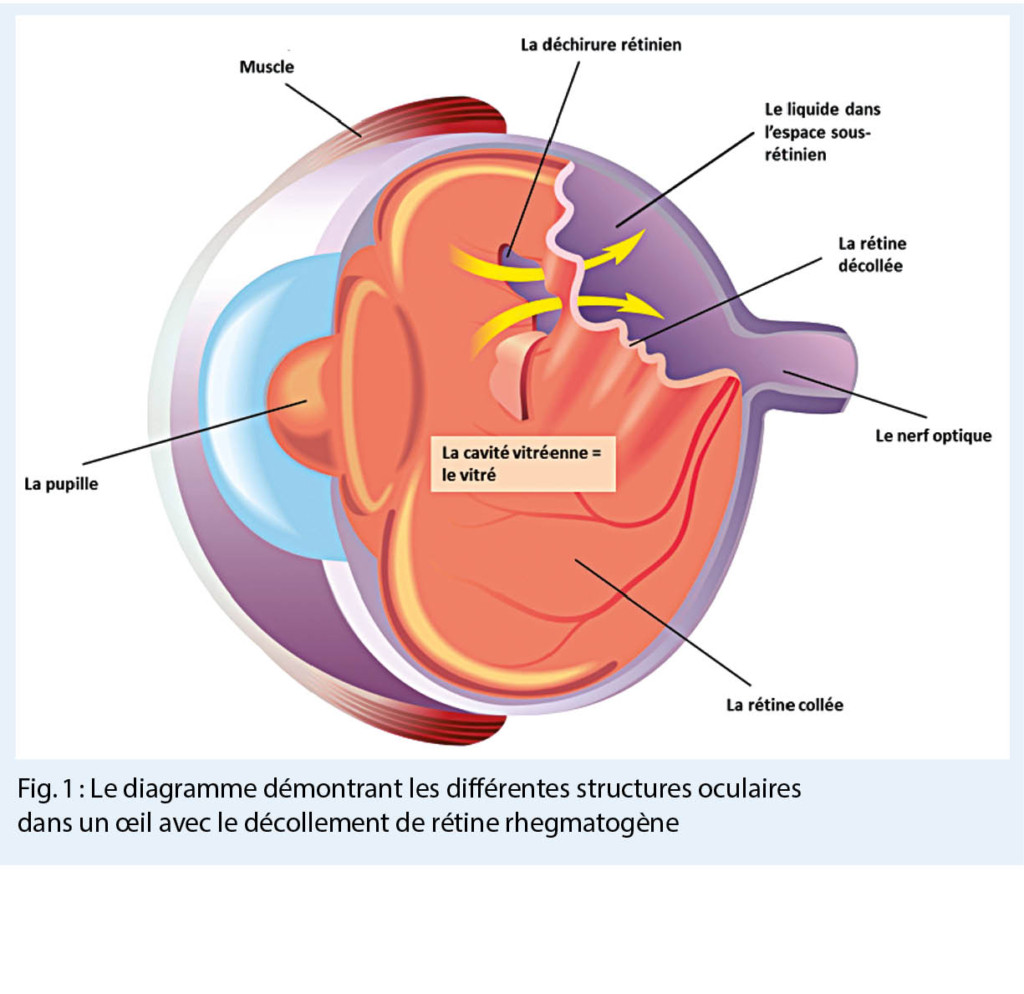

Le décollement de rétine est la conséquence de la séparation de la rétine neurosensorielle de l’ épithélium pigmentaire rétinien, causée par la présence de liquide dans l’ espace sous-rétinien (1).

- primaire ou rhegmatogène, causé par la présence d’ une déchirure rétinienne (rhegma, grec – rupture, fissure, déchirure), et donc pas dû à une maladie (fig. 1) (1).

Les décollements de rétine rhegmatogènes (DR) (fig. 1) sont les plus fréquents, et nous allons nous concentrer sur eux.

L’ incidence du DR est estimée à 1 : 10 000 par an, augmentant d’ environ 3,5% à 5,8 % durant la première année et de 9 % à 10 % dans les 4 ans qui suivent dans l’ œil controlatéral (2). Les déchirures rétiniennes, à l’ origine de la plupart des DR, sont le résultat d’une traction vitréo-rétinienne dynamique sur la rétine périphérique (1) (fig. 1).

L’ influence de divers facteurs, comme l’ âge ou une myopie élevée, peut entraîner des modifications dans la structure du vitré, où des poches remplies de liquide se forment dans un gel auparavant homogène (ce processus est appelé liquéfaction ou synérèse) (3). Le liquide pénètre dans l’ espace entre le vitré et la rétine, provoquant le collapse du vitré et sa séparation de la rétine, d’ abord aux endroits où la connexion entre le vitré et la rétine est le plus faible. Lorsque le vitré se sépare de la rétine (processus normal et physiologique avec l’ âge), certaines parties de la rétine subissent une traction importante ; c’ est à ce moment-là qu’ une déchirure rétinienne peut se produire.

Si le liquide pénètre depuis l’ espace rétro-hyaloïde (l’ espace entre la partie postérieure du vitré et la rétine) par la déchirure rétinienne, la rétine neurosensorielle se sépare de l’ épithélium pigmentaire rétinien et le décollement de rétine rhegmatogène se produit (fig. 1) (1, 3).